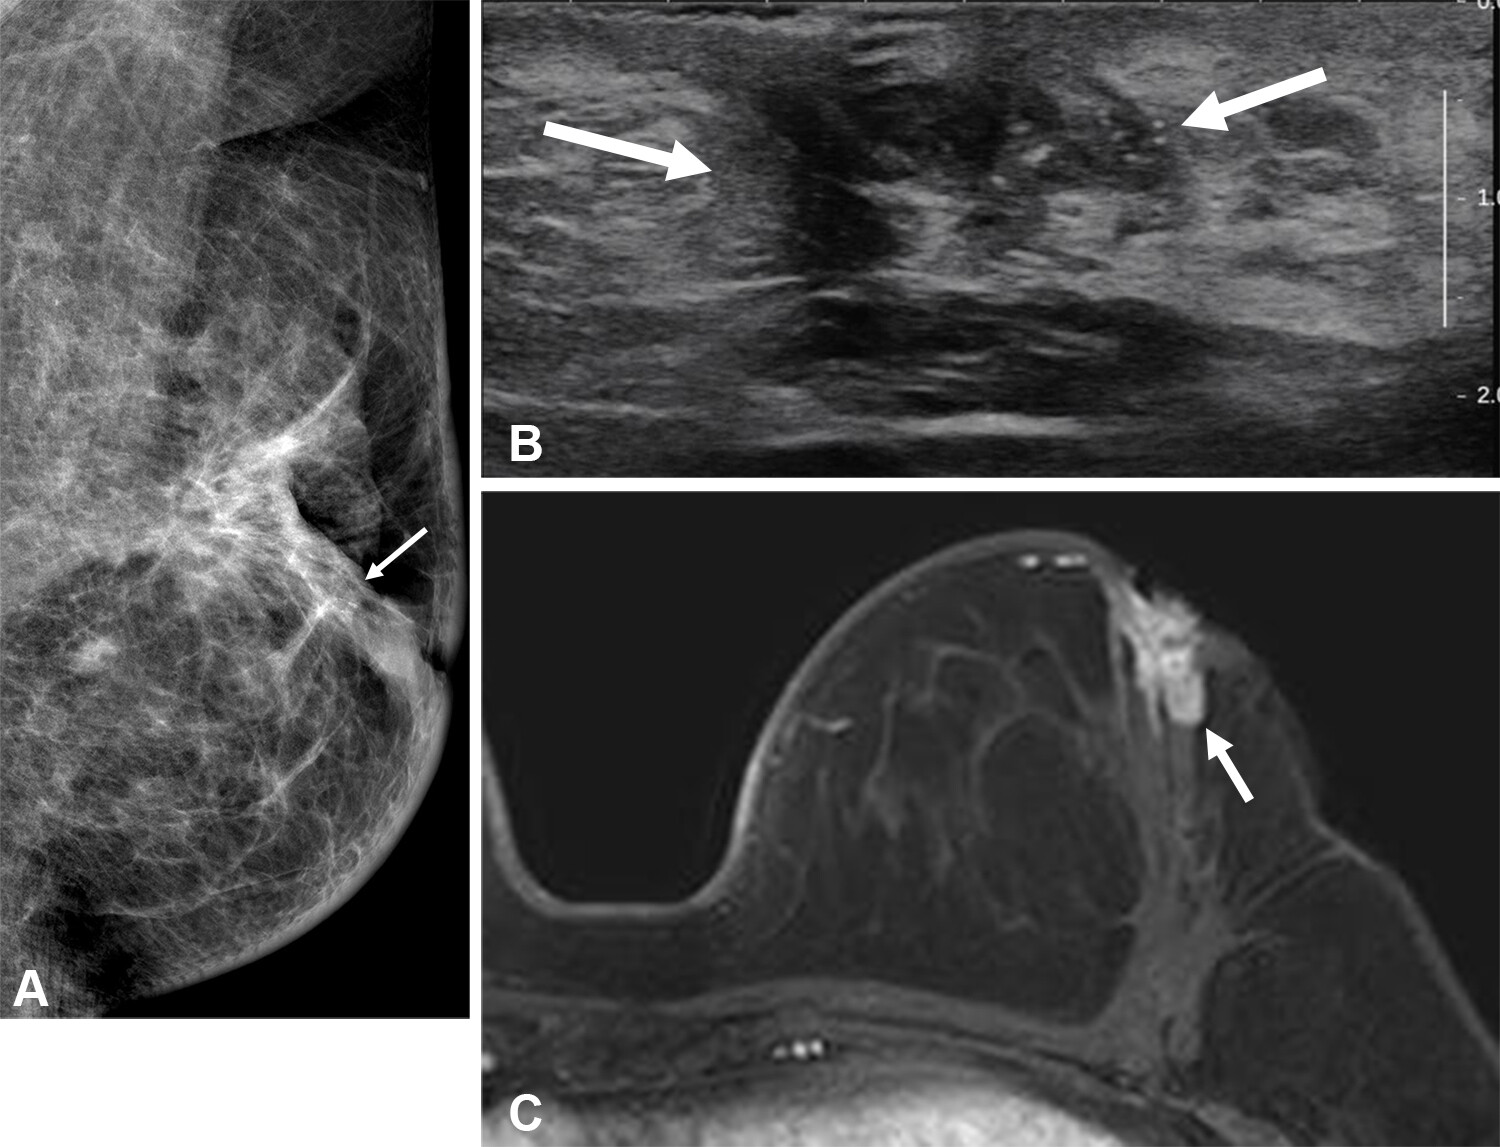

Images of the right breast in a 63-year-old woman with estrogen receptor–low, HER2–positive breast cancer. (A) Mediolateral oblique mammogram obtained before neoadjuvant chemotherapy shows a 5-cm, irregular, spiculated, hyperdense mass (arrows) without calcification in the lower central breast. (B) Axial contrast-enhanced T1-weighted MRI scan obtained before chemotherapy shows two abutting malignant masses (arrows) in the lower central breast. (C) Mediolateral oblique mammogram after chemotherapy shows a decrease in tumor size, with only a biopsy marker (arrow) at the corresponding site. (D) Axial contrast-enhanced T1-weighted MRI scan after chemotherapy shows no residual enhancement in the tumor bed. This radiologic complete response corresponded with pathologic complete response, as determined via pathologic examination after breast-conserving surgery.RSNA